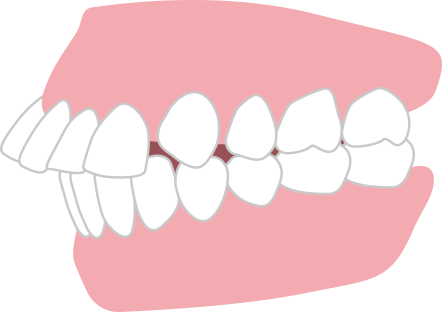

前歯が咬まない 開咬

奥歯で咬めてても前歯同士が当たっていない状態。 めん類や繊維質の食材が咬み切りにくく、また奥歯に負担が集中しやすいため、奥歯の寿命が短くなります。重度の開咬の方は矯正歯科治療が保険適用になります。